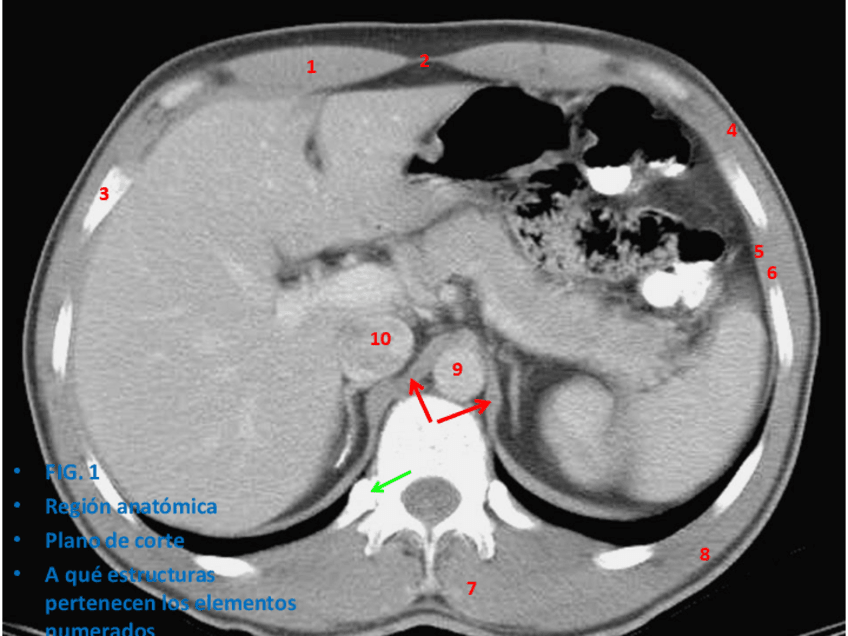

He publicado nuevos apuntes de 1º Anatomía I: tronco y esplacnología: PRÁCTICAS RX

Practica-RX-corregida.pdf

Practica-RX-2-corregida.pdf